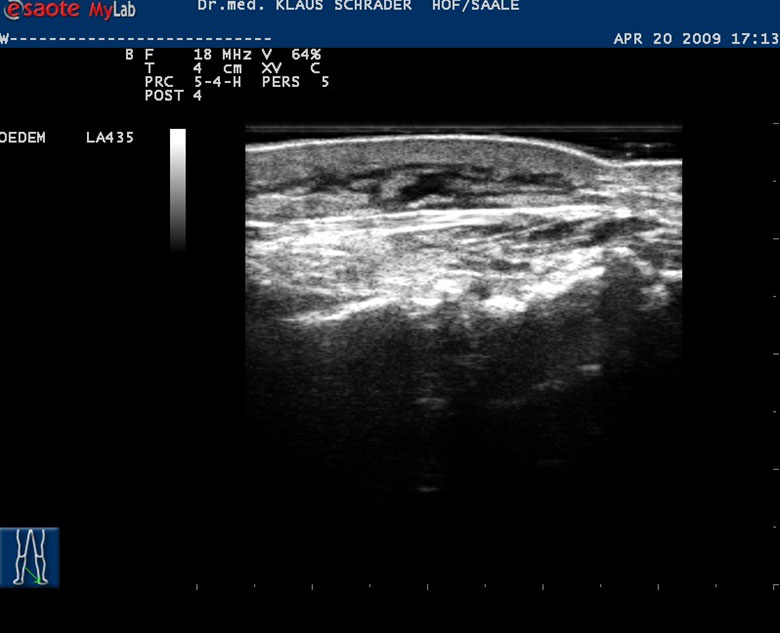

In der Phase 2 der KPE sind regelmäßige Kontrollen notwendig, um einer Verschlechterung rechtzeitig entgegen zu wirken. In unserer Praxis können wir die Beinumfänge berührungslos elektrooptisch vermessen. Mit dem Perometer® sehe ich genau, an welchen Stellen der Umfang ab- oder zunimmt. Die hochauflösende Sonographie zeigt Ödeme, auch wenn wir keine Dellen im Gewebe eindrücken können. Der Erfolg der Behandlungsmaßnahmen kann so, zusammen mit den obligatorischen Berichten der Lymphtherapeuten, objektiv beurteilt werden.